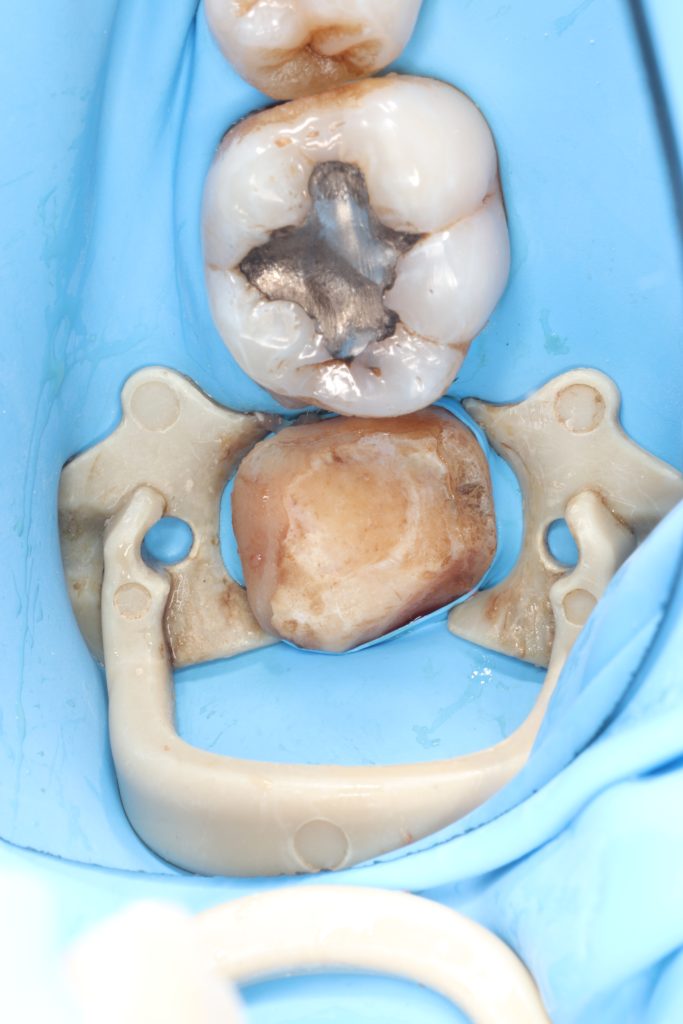

The position of the cej was altered to be 3 mm above bone level

Fiber materials were used to strengthen the furcation area prior to the biobase.The patient’s high saliva density made it necessary to use an intraoral scanner on a rubber dam

In this case where tissue loss is high, we thought that using a resin-containing ceramic block would increase the strength of the tooth in the long term.

1.Gingivectomy

4.Resin-ceramic overlay